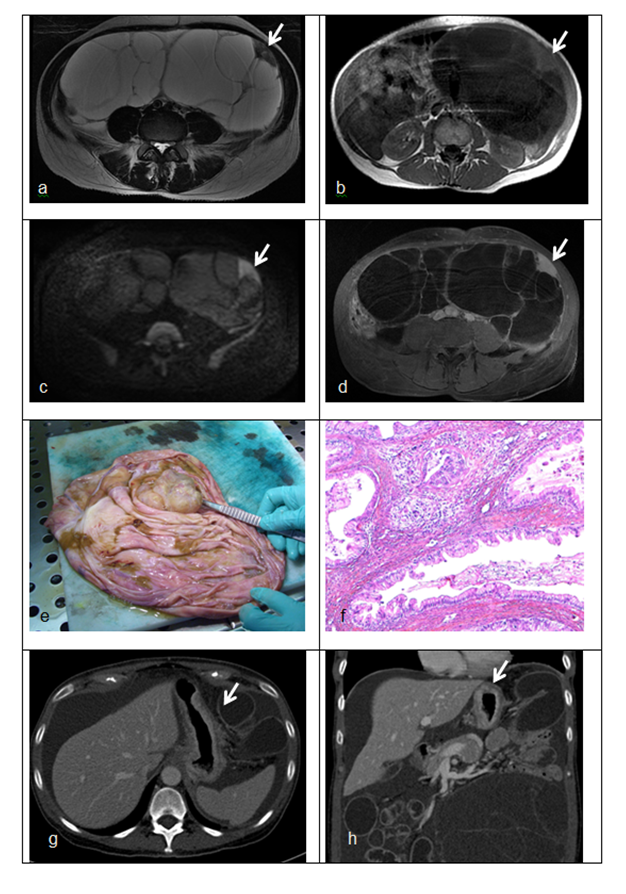

病理学表现

胃癌卵巢转移患者卵巢病灶主要表现为多形性印戒细胞和明显增生的间质细胞密切混合,形成多个界限不清的结节,肿瘤以印戒细胞为主,同时可见腺体、小管、小梁、细胞巢结构。

直肠癌卵巢转移患者肿瘤主要为中等大小的腺体,单个或形成筛状结构,上皮复层,异型性和去黏液性明显,部分区域类似于卵巢子宫内膜样癌的结构。

阑尾肿瘤卵巢转移患者,阑尾主要为低级别黏液性肿瘤,卵巢病灶表现相似,均为丰富的、分割性、细胞外黏液和黏液性增生上皮,黏液上皮表现为杂乱、不规则分布及不完整的腺体,黏液上皮异型性小,单层或局灶复层。

1A:胃癌卵巢转移,可见弥漫分布的多形性印戒细胞和致密的梭形细胞间质 HE × 200;1B:结肠癌卵巢转移,可见肿瘤细胞排列成腺样或筛状结构 HE × 40;1C:结肠癌卵巢转移,可见 ” 污秽性坏死 ” 和 ” 节段性坏死 “ HE × 100;1D:阑尾低级别黏液性肿瘤卵巢转移,可见丰富的、分割性、细胞外黏液和黏液性上皮,上皮细胞轻度异型 HE × 40

2A:胃癌卵巢转移患者细胞角蛋白 7(CK7)阳性;2B:胃癌卵巢转移患者细胞角蛋白 20(CK20)阳性;2C:胃癌卵巢转移患者尾型同源盒转录因子 2(CDX2)阳性;2D:结肠癌卵巢转移患者 CK7 阴性;2E:结肠癌卵巢转移患者 CK20 阳性;2F:结肠癌卵巢转移患者 CDX2 阳性